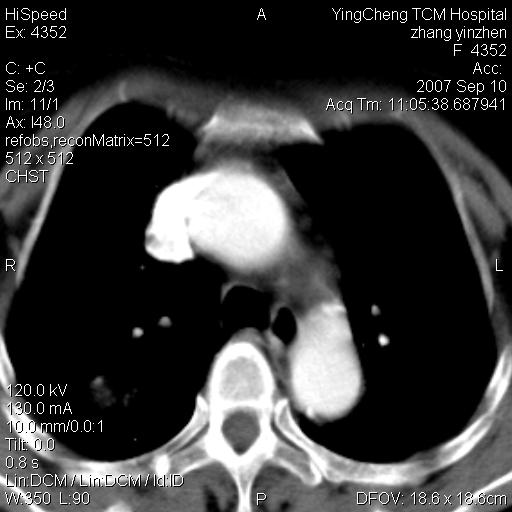

以下是引用卜一在2007-9-18 14:41:00的发言:[br]右肺肿块:毛刺+胸膜凹陷征+供血血管+浅分叶+强化。支持:周围性肺癌 !另:左侧甲状腺腺瘤!

以下是引用夏季在2007-9-18 11:00:00的发言:[br]1。右肺肿块,周围有短毛刺,肺门侧有血管与其相连,胸壁侧有胸膜凹陷征,考虑周围性肺癌 2。左侧甲状腺软组织肿块,内有高密度钙化灶,考虑左侧甲状腺腺瘤。